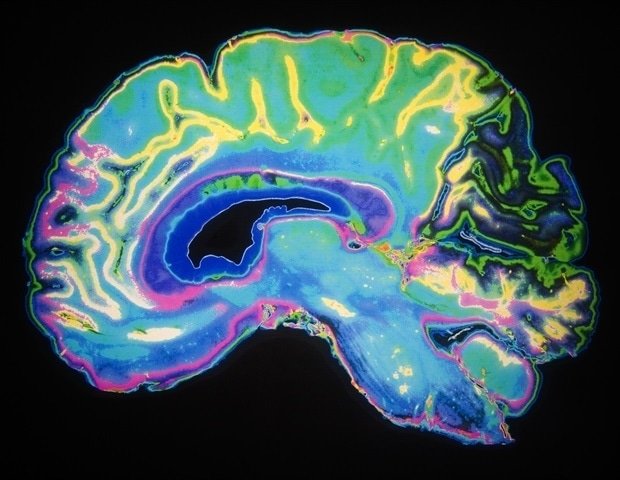

How is Jannik Sinner able to hit the ball at exactly the right time and with incredible precision? And how do we perceive the duration of events around us in everyday life? The answer lies in how the brain constructs our perception of time, as shown in a study published in PLOS Biology by Valeria Centanino, Gianfranco Fortunato, and Domenica Buetti. Starting with what we see, such as the approach of a ball, temporal information is processed by the brain through progressively more complex stages: occipital visual cortex, parietal and premotor areas, and finally frontal areas.

By using high-field functional magnetic resonance imaging (fMRI) and measuring time perception in healthy volunteers, researchers have uncovered what happens in the brain when estimating the duration of a visual stimulus. “Our results show that time perception is not a single process, but the result of multiple processing stages distributed throughout the cerebral cortex,” the authors explain. “From encoding physical duration to constructing a subjective experience of time, each stage contributes in a different way.”

Initially, the occipital visual cortex encodes duration through graded (monotonic) neural responses. The longer the stimulation, the stronger the neural response. This information is then translated into selective (unimodal) representations in the parietal and premotor cortices, where different neural populations respond preferentially to certain durations, allowing for a ‘reading’ of time. Finally, higher-order regions such as the frontal cortex and anterior insular cortex are involved in subjective categorization of duration and shape how we perceive time.